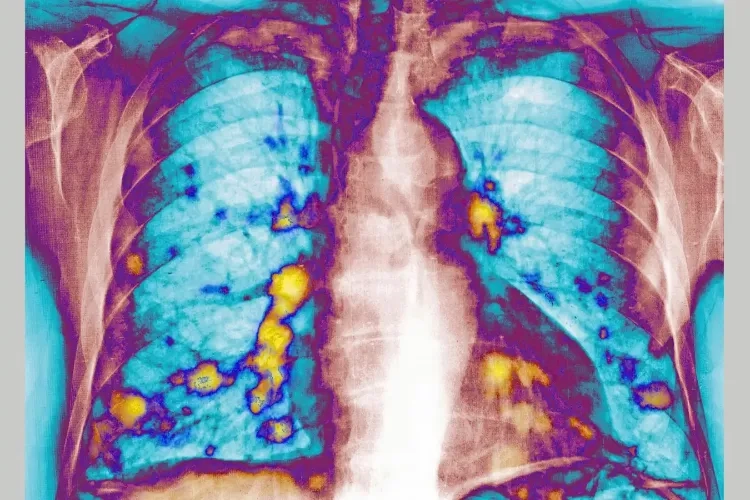

你很难把“感冒”和“抗癌”联系在一起——毕竟前者是让人擤鼻涕的小毛病,后者是谈之色变的绝症。但伦敦帝国理工学院的实验室里,一组小鼠实验颠覆了这个常识:感染过呼吸道合胞病毒(RSV,就是那种让婴幼儿感冒的常见病毒)的小鼠,肺部乳腺癌转移结节数量比对照组少了65%到70%。更关键的是,这种保护不是靠直接杀死癌细胞,而是给肺部布下了一张让癌细胞“落不了脚”的网。这张网的核心,是一种叫I型干扰素的免疫蛋白。它到底是怎么把普通感冒的免疫反应,变成抗癌转移的防线的?

实验数据直白得惊人:给小鼠鼻腔滴入纯化的I型干扰素,效果比RSV感染还要好一点;而如果敲除小鼠的I型干扰素受体,哪怕感染RSV,癌细胞照样能在肺部顺利扎根。这说明,真正起作用的不是病毒本身,而是它触发的这场干扰素主导的肺部微环境改造。